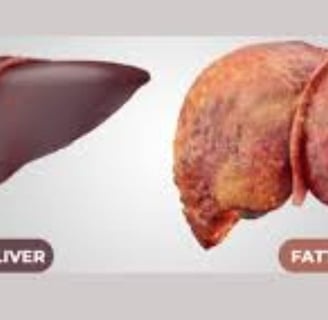

مرض الكبد الدهني، المعروف أيضًا باسم مرض الكبد الدهني غير الكحولي (NAFLD)، يتضمن تراكم الدهون الزائدة في الكبد.

يتميز مرض الكبد الدهني بوجود فائض من الدهون في الكبد، حيث تعتبر الاضطرابات الأيضية والاستهلاك المفرط للكحول من عوامل الخطر الرئيسية.

هناك نوعان رئيسيان من الكبد الدهني: مرض الكبد الدهني غير الكحولي (NAFLD) الذي يتضمن تراكم الدهون في الكبد، ومرض التهاب الكبد الدهني غير الكحولي (NASH) الذي يترافق مع علامات الالتهاب وتلف خلايا الكبد.

التليف: يتكون نسيج ندبي نتيجة الالتهاب الذي يؤدي إلى تلف الكبد.

تليف الكبد: حيث يتم استبدال الأنسجة السليمة بنسيج ندبي.

سرطان الكبد: يمكن أن يتطور نتيجة لهذه الحالات.